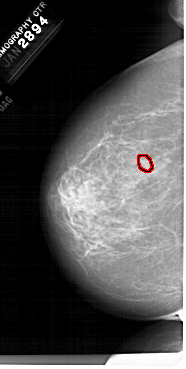

A_1679_1.LEFT_MLO

LEFT_MLO LINES 6781 PIXELS_PER_LINE 3631 BITS_PER_PIXEL 12 RESOLUTION 43.5 OVERLAY

FILE: A_1679_1.LEFT_MLO.OVERLAY

TOTAL_ABNORMALITIES 1

ABNORMALITY 1

LESION_TYPE MASS SHAPE LOBULATED MARGINS OBSCURED-CIRCUMSCRIBED

ASSESSMENT 4

SUBTLETY 3

PATHOLOGY BENIGN

TOTAL_OUTLINES 1

BOUNDARY